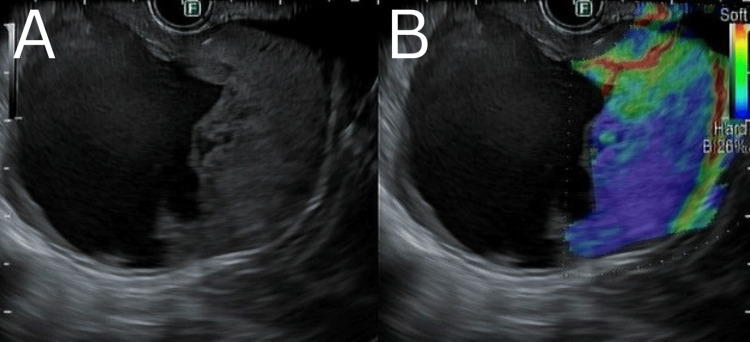

2.疾病诊疗过程EUS检查所见与鉴别诊断:患者接受超声内镜(EUS)检查,于胰尾部探及一大小约60×60 mm的异质性占位,其来源难以明确(图3)。病变中心呈无回声,符合囊性液体表现,其周围散在少量高回声影,考虑为胆泥或碎屑沉积。病变边缘可见低回声区域,提示存在实性成分。对该占位的囊性部分行穿刺抽液,获约20 ml稀薄暗红色液体;同时对实性部分行细针穿刺活检。EUS下未见门静脉周围、胰腺周围及腹腔干区域存在明显恶性淋巴结。胰尾部可见高回声条索影,胰管形态及内径正常。胆囊内可见多发点状高回声,符合结石与胆泥声像。胆总管内径正常,未见明确充盈缺损。胰头形态结构未见异常。因该占位来源难以确定,鉴别诊断需重点考虑胰腺来源的恶性肿瘤,如胰腺黏液性肿瘤,以及可能来源于胃后壁或胰腺的GIST。

图3. 超声内镜图像。

(A)混合性囊实性病变;(B)弹性成像示实性部分硬度增高,符合肿块特征。